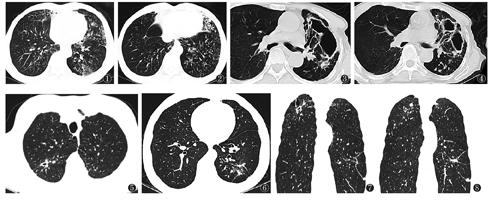

肺内病变以支气管扩张伴周围小叶中心结节为主(图1,图2),可合并空洞、斑片影、纤维条索灶及其他征象。支气管扩张及结节通常见于右肺中叶、左肺舌段,常累及3个或以上肺叶,也可无明显叶段倾向性;结节以小叶中心结节为主,对位于胸膜下;支气管扩张与小叶中心结节同时存在,多为小叶中心型柱状扩张,管壁增厚,扩张管腔内可有黏液栓,周围可伴斑片影,周围肺组织结构扭曲变形不明显。

以肺内斑片影及支气管播散灶为主(图5,图6,图7,图8),可合并空洞、支气管扩张等。特点如下:斑片影及支气管播散灶多叶段受累,以双肺上叶尖后段、下叶背段为主;可合并支气管扩张,斑片影内可有空洞形成。